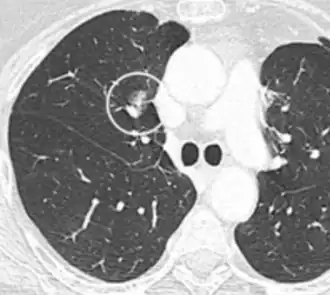

Chest X-ray showing a solitary pulmonary nodule (indicated by a black box) in the left upper lobe.